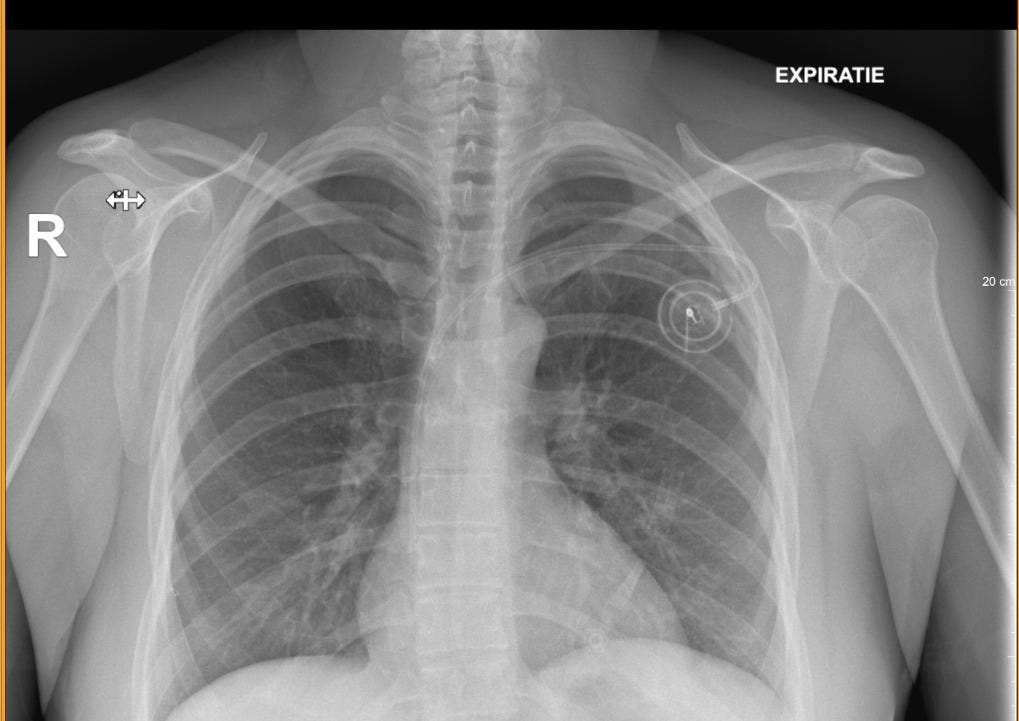

Quando il 6 novembre 2023 sono andata in ospedale, il mio percorso di terapia per guarire dal cancro era già iniziato: il giorno dopo avrei cominciato con il primo ciclo di chemioterapia. Avevo fatto esami su esami, per escludere la presenza di metastasi, e capire il profilo genetico del mio tumore. Il piano di chemioterapia era chiaro, il protocollo ben definito. La primissima cosa da fare era inserire un port-a-cath dentro il mio corpo: un accesso venoso impiantabile attraverso il quale estrarre il mio sangue e inserire farmaci citotossici, uno dopo l’altro, direttamente dentro una vena bella grossa, nel mio caso la succlavia. Poi lo avrei usato anche per ricevere sangue, ma questo non lo sapevo ancora.

È stato il primo intervento fisico che ha modificato il mio corpo da quando avevo scoperto di avere un tumore: lo sentivo, il tumore dico, sotto le mie dita, sotto la doccia, quando mi vestivo, d’improvviso nel mezzo di una qualunque attività. Ma il mio corpo non era ancora stato inciso. Sarebbe cambiato, lo sapevo, ma inserire un port è stato un po’ la prova del nove: non è un sogno, non andrà via da solo, ci vorrà un po’ di lavoro, un pizzico di fortuna, una o due manovre, su questo corpo monello ma forte. In un episodio dal titolo “Scatti ribelli” ho pubblicato una foto del mio port, la trovate qui.

Il port viene inserito in day hospital, con un piccolo intervento chirurgico in anestesia locale. Avevo una paura pazzesca, il 6 novembre 2023, ma io sono sempre stata una fifona in ospedale. Ho sempre pensato di soffrire di una cosa conosciuta in inglese come mirror pain - un dolore specchio? non lo so, non ho mai approfondito, ma vi posso dire benissimo che cosa provo. Io arrivo in ospedale, vedo una persona che si è fratturata una gamba, la destra, ad esempio, e io improvvisamente non riesco a muoverla, la mia, di gamba destra. Sento dolore al petto se è il petto che è fasciato, mi scoppia la testa, se è la testa che mostra una ferita. In ospedale soffro, devo chiudere gli occhi di continuo, distogliere lo sguardo. Anche per questo non riesco a guardare serie televisive mediche, per me è una tortura. Una risposta empatica ridicola forse legata a una maggiore attività dei miei neuroni specchio, o forse è solo che sono sempre stata una fifona e il mio corpo ha deciso di trovare una scusa così, per dirsi che va bene lo stesso. Chi lo sa. Il port viene inserito in day hospital, dicevo, e io avevo una gran paura. Mio marito, che non mi aveva lasciata un attimo da sola dal giorno della diagnosi, non poteva proprio venire in ospedale, quel giorno lì, cosi è venuto un amico. Quando all’accettazione, in chirurgia, hanno chiesto un contatto di emergenza, ho dato il suo numero di telefono. Ho anche detto che sarebbe stato lui a portarmi a casa, dopo l’anestesia e tutto (se non muoio sotto i ferri - ho pensato). L’infermiera mi ha chiesto se questa persona fosse mio marito, il mio compagno. Mi sono limitata a dire di no. Poi ha aggiunto qualcosa tipo - is he just a friend? Non lo so di preciso perché le importasse il nostro grado di parentela. Io in preda alle mie visioni da bisturi, sangue e ferite non ho riflettuto molto e le ho risposto - yes, sure, just a friend. È solo un amico, le avevo detto.

Quel 6 novembre 2023 non sono morta - la mattina dopo sono svenuta, ma questa è un’altra storia. Il port è ancora sotto la mia pelle, anche se al momento non ricevo farmaci in endovena. Lo lasciamo ancora un po’ lì, non c’è fretta - dice sempre l’oncologo - e io ogni volta penso che i miei tempi e i suoi sono proprio due robe diverse.